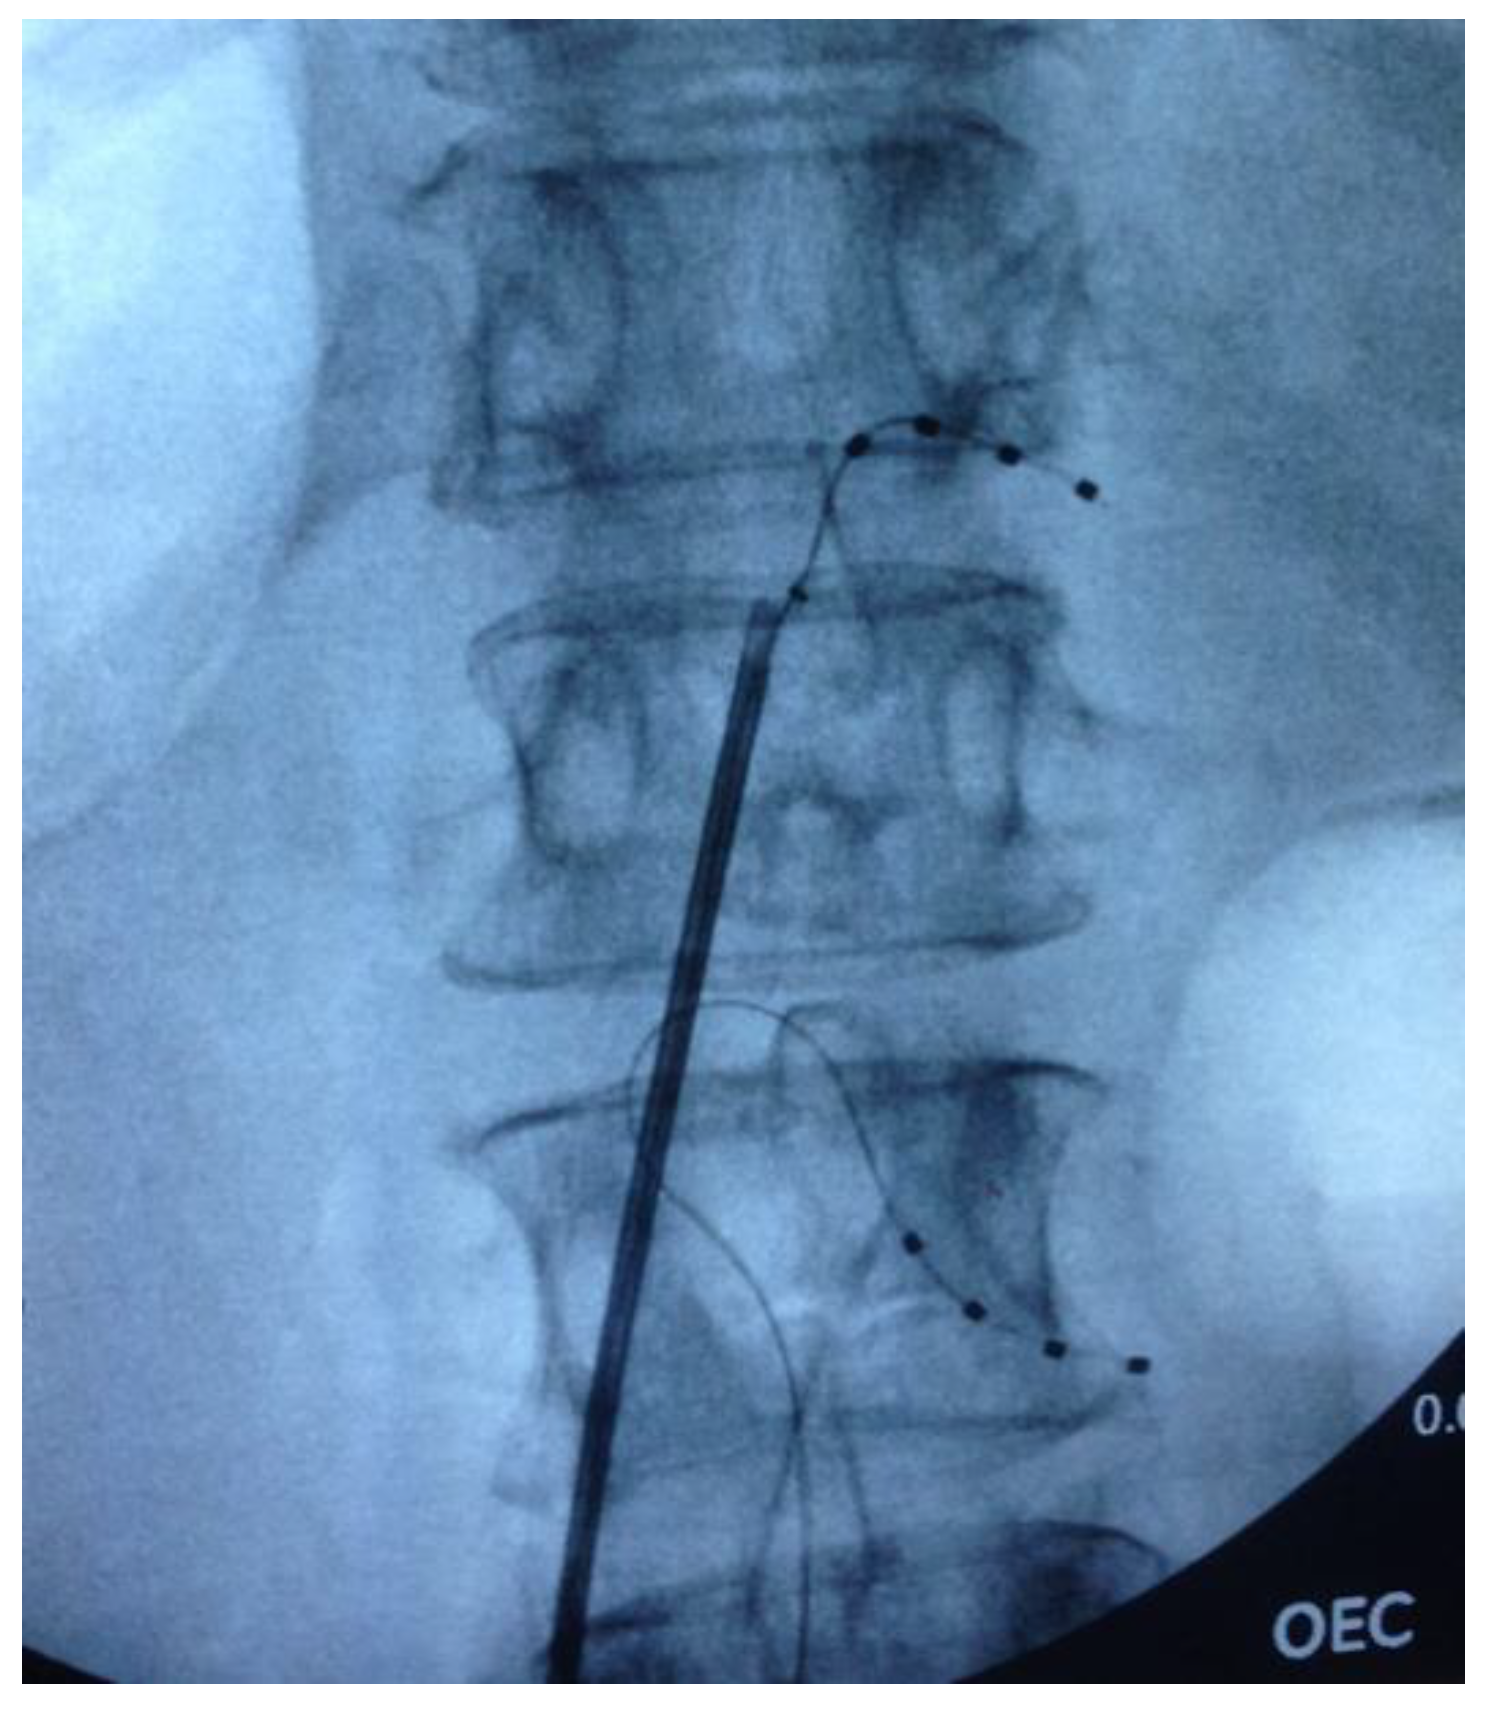

2.2. Surgical Procedure

The DRG stimulators were implanted under local anaesthetic with light sedation (propofol) in the prone position. Under fluoroscopic control, a delivery sheath was used to enter the epidural space, and a DRG Axium® lead (Abbott Laboratories, Sunnyvale, CA, USA) was introduced under X-ray guidance into the appropriate nerve root exit foramen, so that the electrode contacts were positioned over the dorsum of the DRG in the dorsal part of the foramen. Sedation was weaned and the leads were tested for efficacy prior to re-sedation. Subsequently, when anteroposterior and lateral X-rays had confirmed satisfactory position (See Figure 1), a strain-relief loop was fashioned in the spinal canal, and the wires were tunnelled to an implantable pulse generator (IPG) that was placed subcutaneously remote from the spine.

Figure 1. Fluoroscopic image of intra-operative dorsal root ganglion (DRG) lead placement at T12 and L2 on the right side.